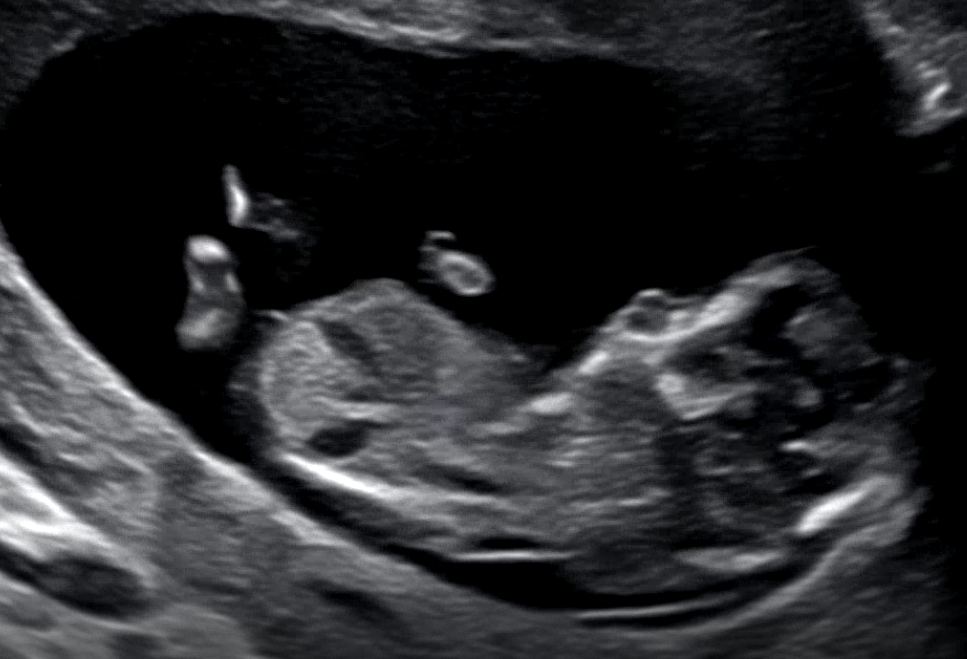

12주차 성별좀봐주세용!!

투표 부탁드려요🥰